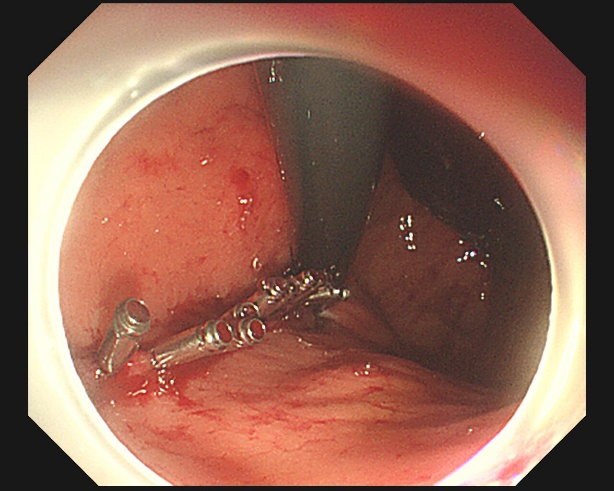

小张病情十分凶险,李琨琨立即为他安排急诊,内镜下,金属夹夹闭止血,术中,李琨琨惊讶地发现,小张醉酒呕吐导致贲门黏膜撕裂,创面居然长达 10 公分,局部可见裸露血管,并活动性出血。

李琨琨技术娴熟的为创面一一打上金属夹,就好像把伤口针针缝合住一样,止血效果立竿见影,小张的血压终于稳定!